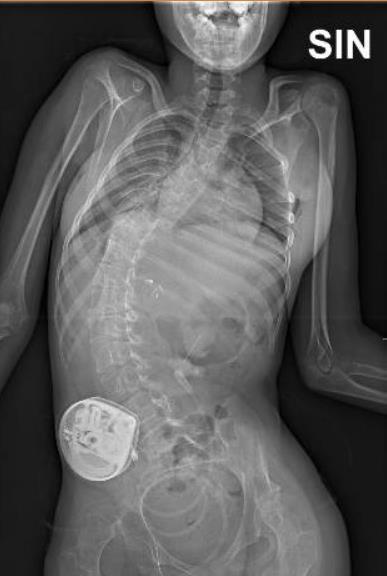

Spinal deformities after SDR via multilevel laminectomy and laminoplasty

Thirty-one children (31/313 = 24%) had a VP shunt as part of the management of hydrocephalus. Five children (5/31 = 16%) had infection in 1 of their systems

• Worsening of scoliosis